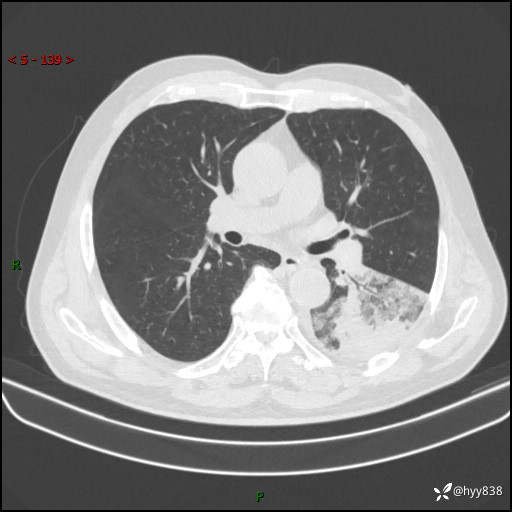

59岁/男,发热伴咳嗽3天。白班偶遇,“大叶性肺炎”,病原体挑战---结果公布~

【患者信息】:59岁/男

【主诉】:发热伴咳嗽3天

【现病史及既往史】:患者3天前无明显诱因出现发热,体温最高达38.6℃,伴有咳嗽,干咳为主,感乏力、肌肉酸痛,无明显头晕头痛、鼻塞、流涕、呼吸困难、胸痛、恶心呕吐、腹痛腹泻、尿频尿急等不适,于当地诊所输液治疗3天感症状无好转,仍有间断发热、咳嗽,现为求进一步诊治,于我院门诊就诊,门诊以“发热待查”收入我科进一步诊治。 患者自发病以来,精神、饮食、睡眠欠佳,大小便正常,体力、体重无明显变化。

【检查】:胸部CT平扫